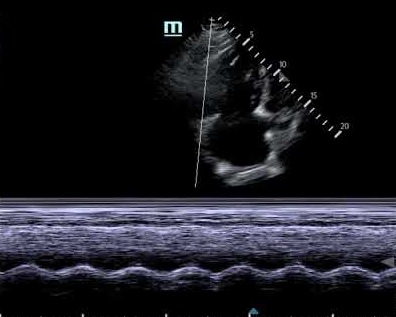

TAPSE Echocardiography Measurement

For the proper measurement, first of all, take an apical four-chamber sight of the heart. After that locate the tricuspid annulus and directly place the M-mode cursor on the lateral side of this specified point. It will allow the measurement of the overall distance of the displacement of the maximal longitudinal aspect. Keenly observe the three consecutive cardiac cycles and evaluate the average of these continual cycles.